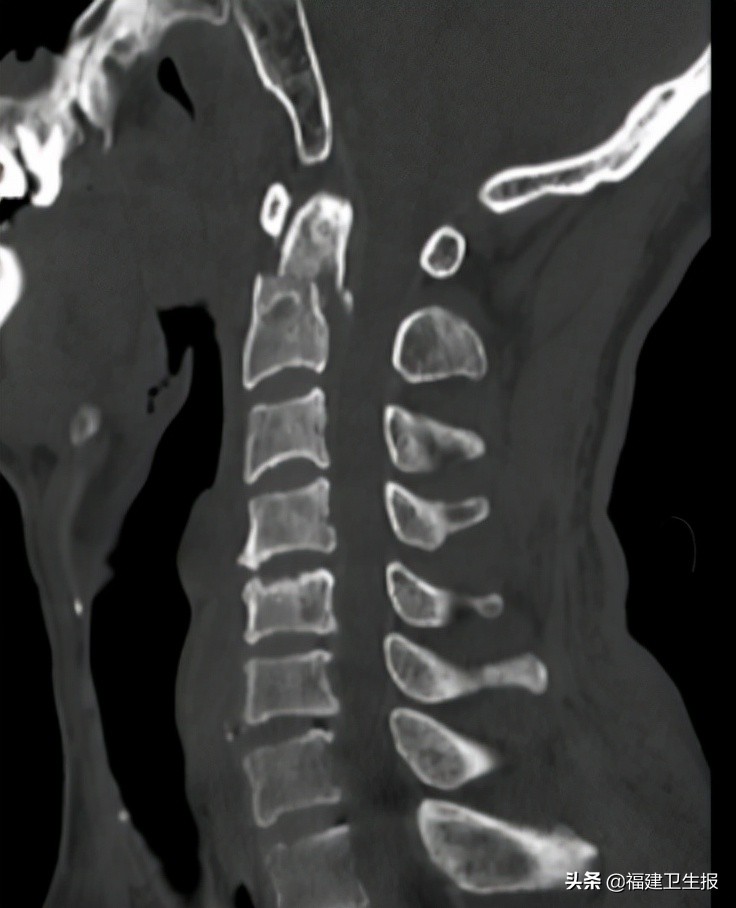

50岁的刘某因不慎摔伤致颈部疼痛、颈部活动受限,并有双侧上肢无力、麻木,就诊于福建医科大学附属第一医院泉港总医院。急诊颈椎CT检查报告为枢椎齿状突骨折伴寰椎椎体后脱位。

入院后,福建医科大学附属第一医院下派脊柱外科专家朱希田副主任医师接诊。进一步明确患者为高位枢椎齿状突骨折、寰椎后脱位并多节段颈脊髓损伤、多节颈椎椎体压缩性骨折并多节段颈椎间盘突出压迫颈脊髓,情况危急。

▲患者术前X光

▲CT